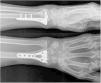

Intervención: Luego de 8 días del trauma se le practicó reducción abierta más osteosíntesis con placa de bloqueo volar (fig. 3). En control de ortopedia a los 15 días del posquirúrgico presenta limitación funcional total de mano y muñeca izquierda, ocasionada por el dolor y el edema. Después de 21 días del posquirúrgico inició el proceso de rehabilitación, asistió a 10 sesiones de terapia física y a 10 sesiones de terapia de movilización pasiva con órtesis robótica (fig. 4).

Resultados: inicialmente se encontró una puntuación en la escala DASH de 68.38 y en la escala EVA de 10; después de 4 semanas de rehabilitación complementada por órtesis robótica, mejoró la funcionalidad según DASH a 7.35 y disminuyó el dolor según EVA a 0. Además, mejoró los arcos de movilidad articular de la muñeca en extensión de 10 a 50 grados, en flexión de 35 a 45 grados, la desviación radial de 15 a 30 grados, y la desviación ulnar de 15 a 20 grados. La paciente inició las actividades de la vida diaria luego de la tercera semana de rehabilitación, y no se reportaron eventos adversos durante la intervención. (Tabla III y IV)